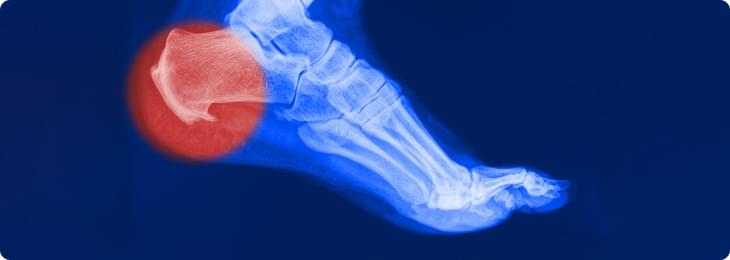

Активность человека снижается, воспалительный процесс затухает и на месте поврежденных волокон возникают костные разрастания, которые видны на рентгенограмме и имеют характерный вид «шпоры».

Вот поэтому это заболевание и называют «пяточной шпорой», хотя сама «шпора» является уже результатом длительно протекающего плантарного фасциита.

Рентгенография пяточной области необходима для исключения перелома, если в анамнезе есть указания на травму. На ранних этапах формирования пяточная шпора на рентгенограмме не визуализируется.